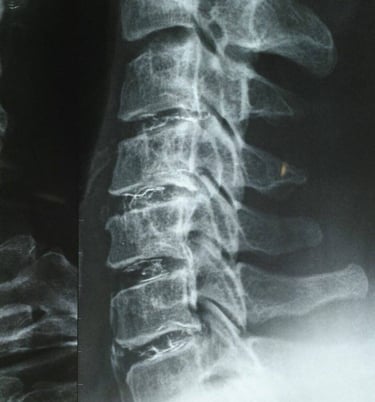

This sterile implantable medical device is based on jellified ethanol in which

an opaque agent in X-rays, the tungsten was added.

To determine the impact of ethanol gel chemonucleolysis (EGCh) on the radiological picture of the treated intervertebral disc...

The results showed a decrease in the size of the protrusion and GI zone in the treated intervertebral disc. The presence of a high-intensity zone (HIZ) on baseline magnetic resonance imaging was found to be a good predictor of the timing and outcome of treatment, and an increase in disc height was observed in adjacent segments.